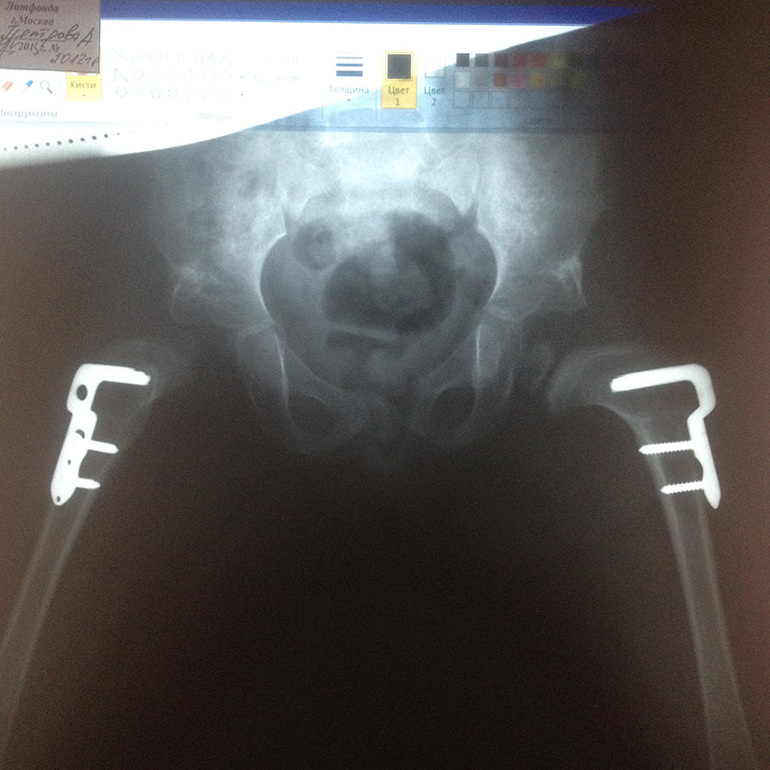

В конце февраля мы вернулись домой, а спустя три месяца (ну, чуть раньше), сделали снимок. В пятницу сделали его. Похоже, что Арина дернулась, либо я ее как-то криво или косо положил, снимок совсем кривой был. Сегодня отправились еще раз, Арину уложила врач-ортопед, на этот раз с отведением и внутренней ротацией. Показали снимок местному ортопеду (мы в клинике Литфонда снимок делали. вообще мы туда к аллергологу ходили, но рентгеновский кабинет совсем рядом, чего бы не сфотографировать))), переслали снимок нашему профессору в Германию. Оба врача сказали, что левая нога хороша, а вот правая так себе. Но про операцию никто и ничего не говорит, говорят, качайте мышцы, делайте массаж и т.д.

Шину оставить только на ночь, а через три месяца совсем без шины.

Ну и снимок прикладываю))